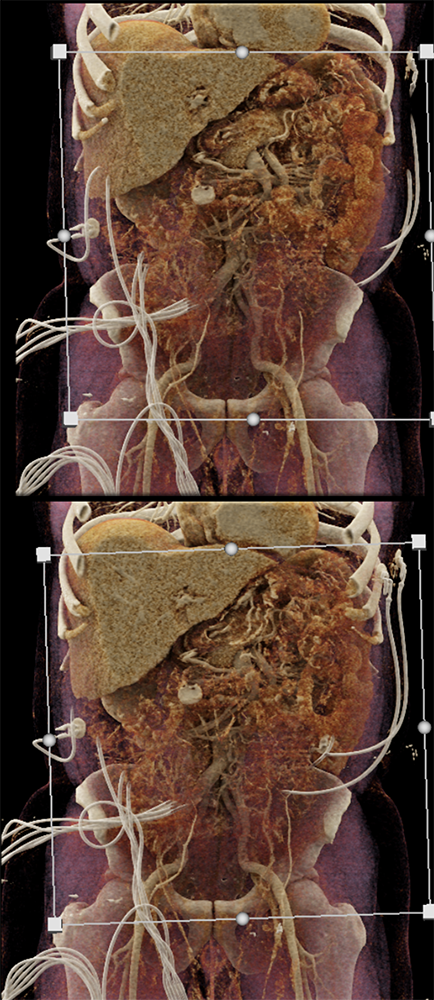

GIST Tumor Jejunum as the Cause of GI Bleeding ![]() |

![]() |